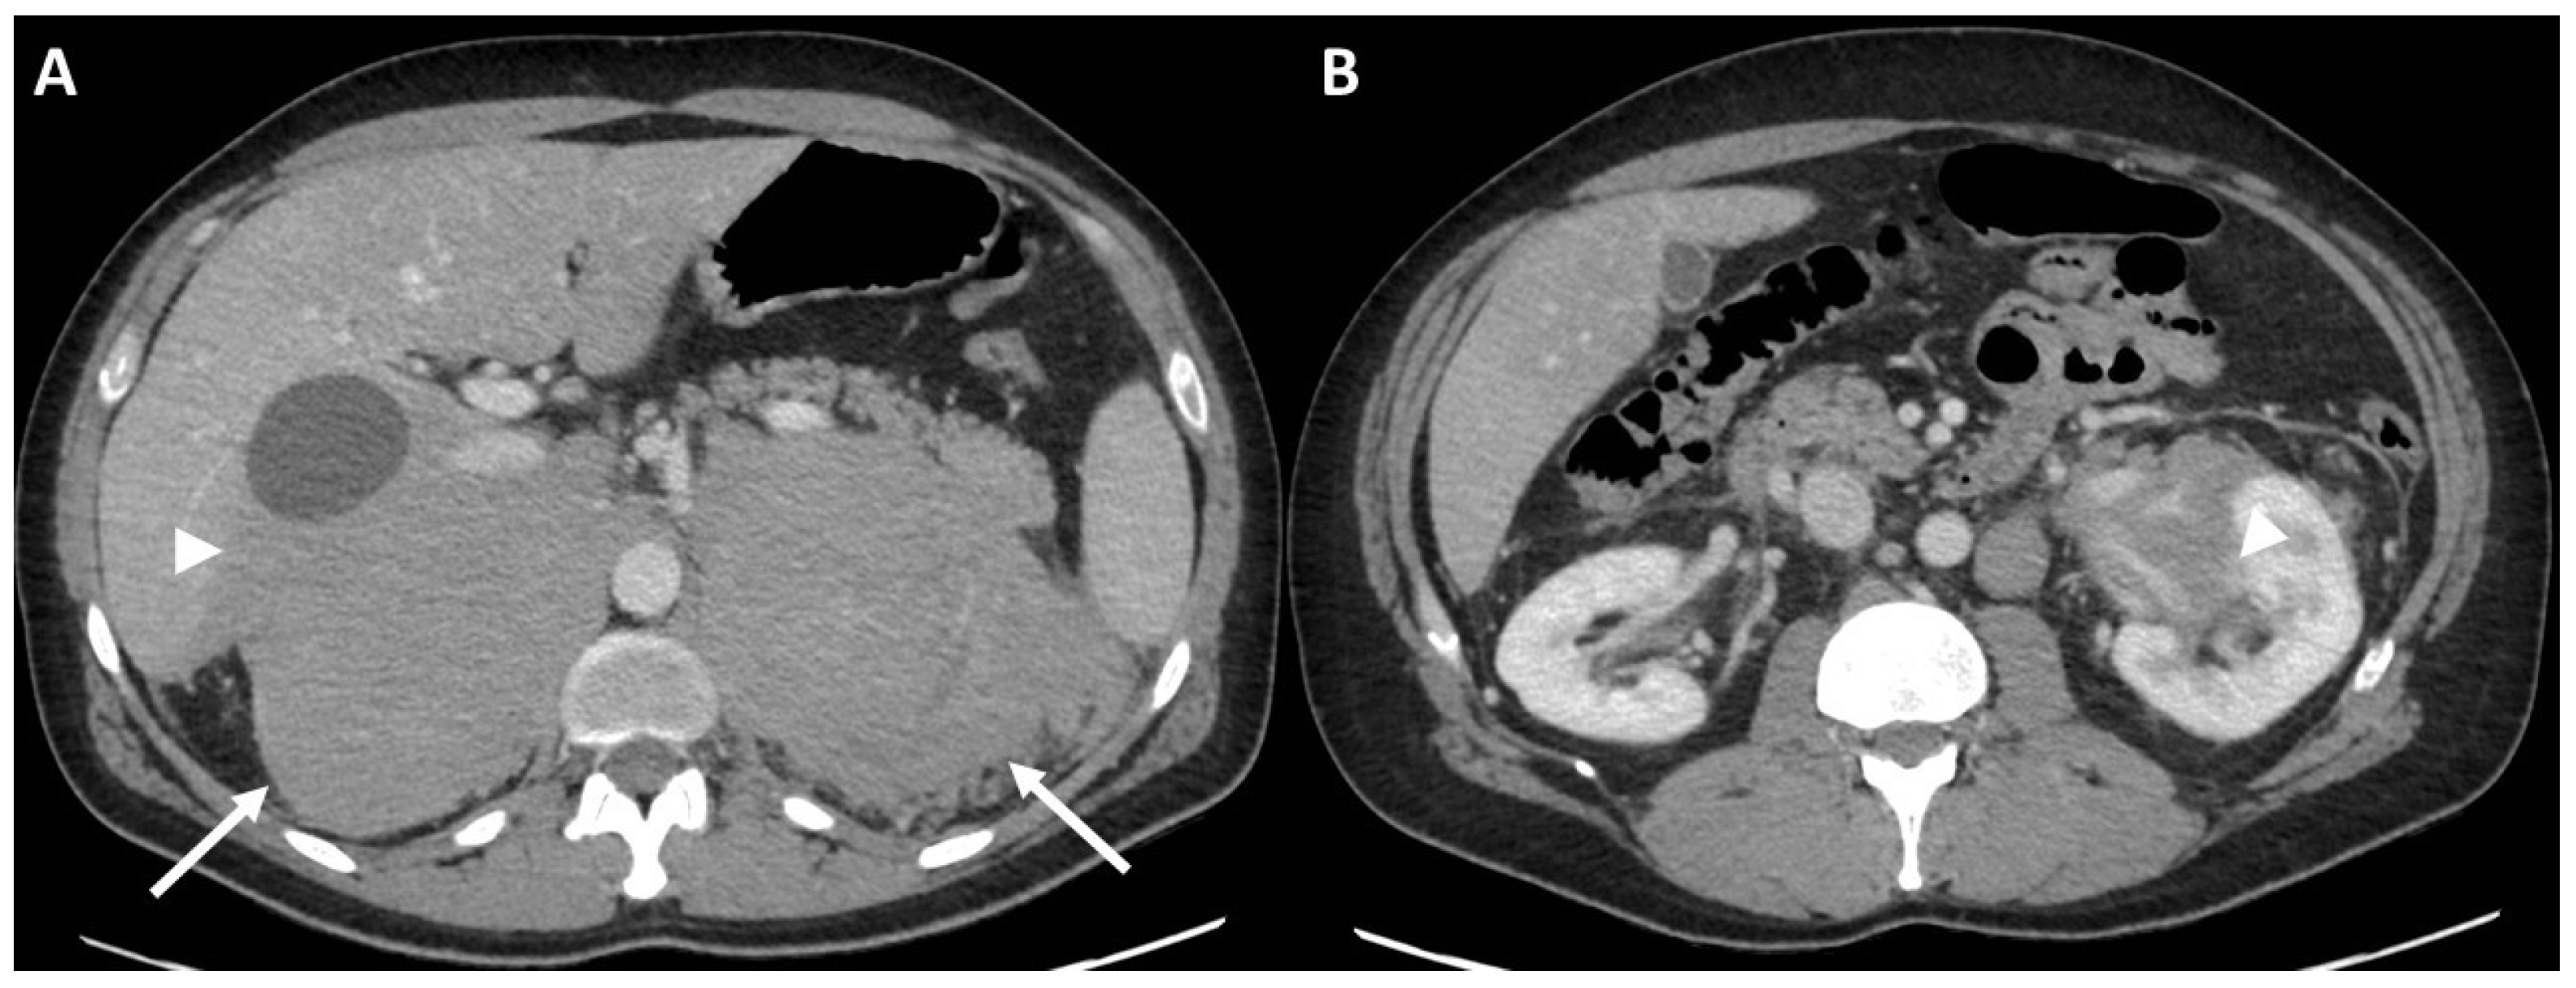

3.2.1. Initial Staging of Disease: Case #1